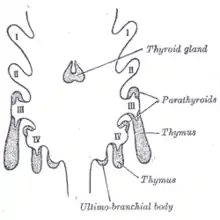

Development

The thymocytes and the epithelium of the thymus have different developmental origins.[4] The epithelium of the thymus develops first, appearing as two outgrowths, one on either side, of the third pharyngeal pouch.[4] It sometimes also involves the fourth pharyngeal pouch.[3] These extend outward and backward into the surrounding mesoderm and neural crest-derived mesenchyme in front of the ventral aorta. Here the thymocytes and epithelium meet and join with connective tissue. The pharyngeal opening of each diverticulum is soon obliterated, but the neck of the flask persists for some time as a cellular cord. By further proliferation of the cells lining the flask, buds of cells are formed, which become surrounded and isolated by the invading mesoderm.[7]

The epithelium forms fine lobules, and develops into a sponge-like structure. During this stage, hematopoietic bone-marrow precursors migrate into the thymus.[4] Normal development is dependent on the interaction between the epithelium and the hematopoietic thymocytes. Iodine is also necessary for thymus development and activity.[8]

The most common congenital cause of thymus-related immune deficiency results from the deletion of the 22nd chromosome, called DiGeorge syndrome.[15][16] This results in a failure of development of the third and fourth pharyngeal pouches, resulting in failure of development of the thymus, and variable other associated problems, such as congenital heart disease, and abnormalities of mouth (such as cleft palate and cleft lip), failure of development of the parathyroid glands, and the presence of a fistula between the trachea and the oesophagus.[16] Very low numbers of circulating T cells are seen.[16] The condition is diagnosed by fluorescent in situ hybridization and treated with thymus transplantation.[15]